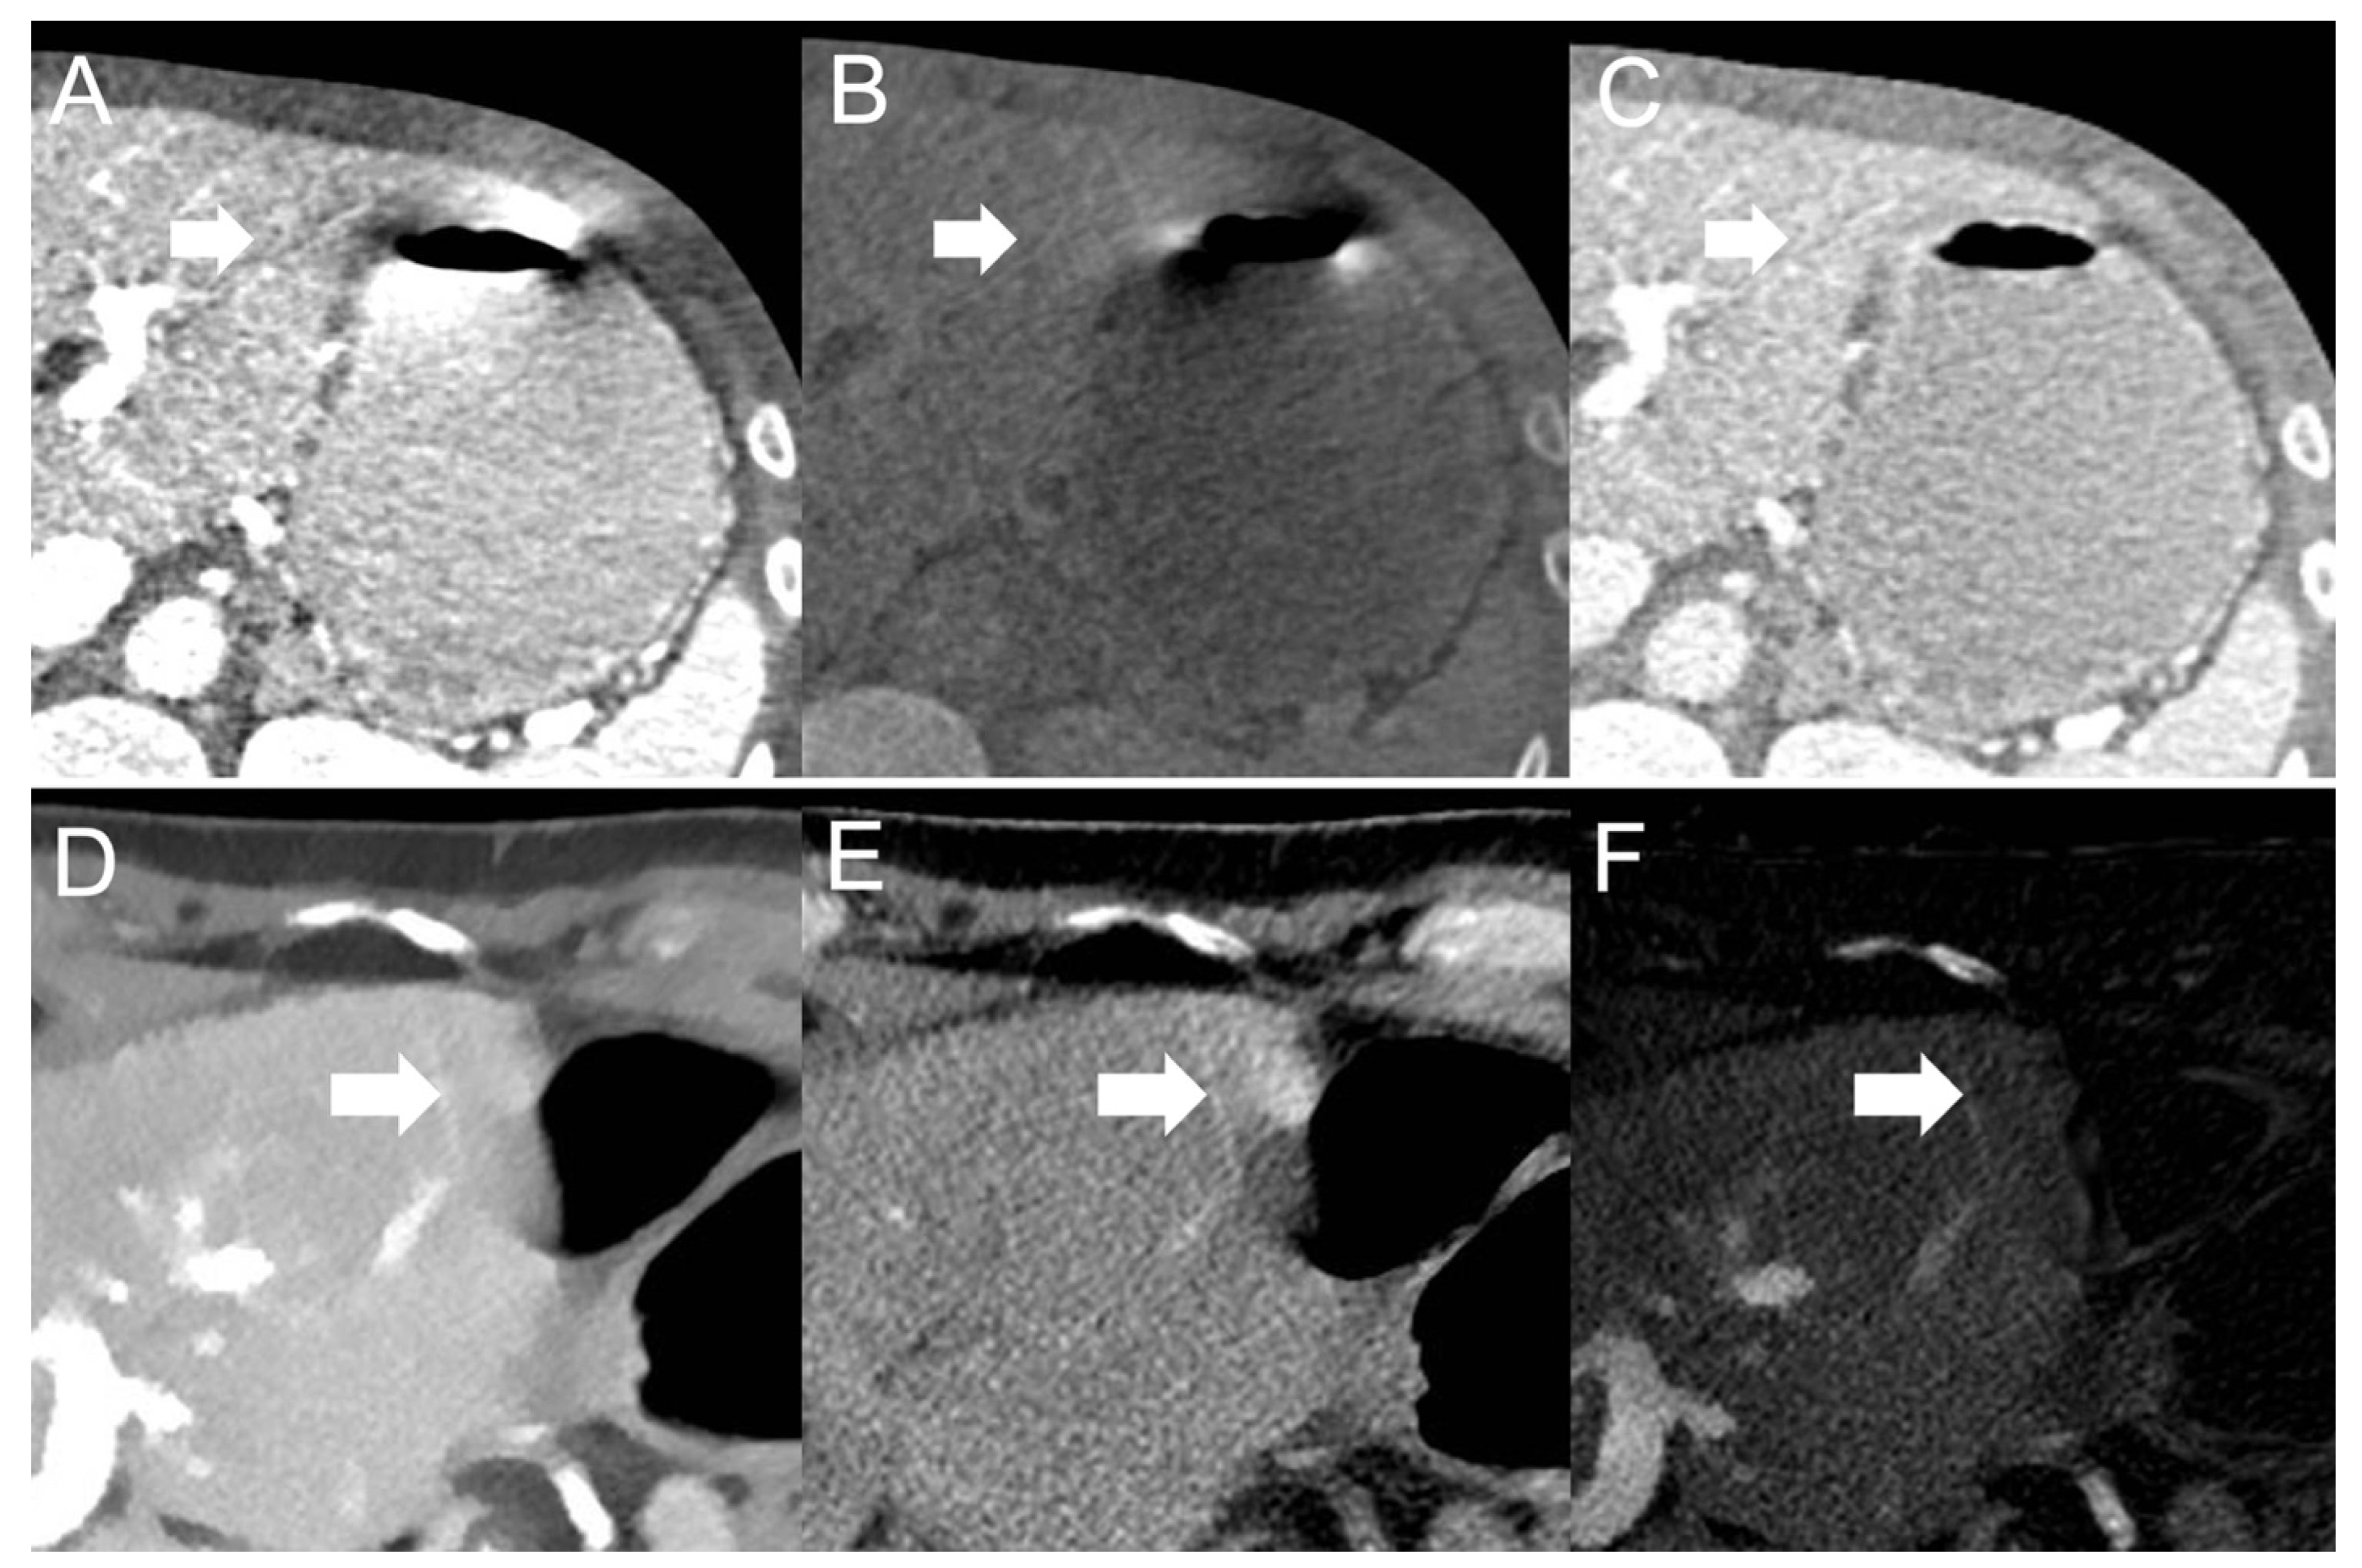

Motionrelated artifacts. (a) Abdominal image obtained without breath Motion Related Artifacts  Important to recognize and understand motion artifacts to identify the physical cause of the problem in a particular clinical situation and. Without mitigation, motion artifact can bias statistical inferences about relationships between connectivity and individual. In this review, we first examine the physical origins of motion artifacts and then summarize the main motion prevention and correction tools currently in use. Motion Related Artifacts.

Grading of motionrelated artifacts after gadoxetate disodium injection Motion Related Artifacts  In this review, we first examine the physical origins of motion artifacts and then summarize the main motion prevention and correction tools currently in use or in. Without mitigation, motion artifact can bias statistical inferences about relationships between connectivity and individual. Movement artifacts compromise image quality and may interfere with interpretation, especially in magnetic resonance imaging (mri) applications. Important to. Motion Related Artifacts.

Grading of motionrelated artifacts after gadoxetate disodium injection Motion Related Artifacts  Important to recognize and understand motion artifacts to identify the physical cause of the problem in a particular clinical situation and. Movement artifacts compromise image quality and may interfere with interpretation, especially in magnetic resonance imaging (mri) applications. There are 2 types of artifacts due to motion: In this review, we first examine the physical origins of motion artifacts and. Motion Related Artifacts.